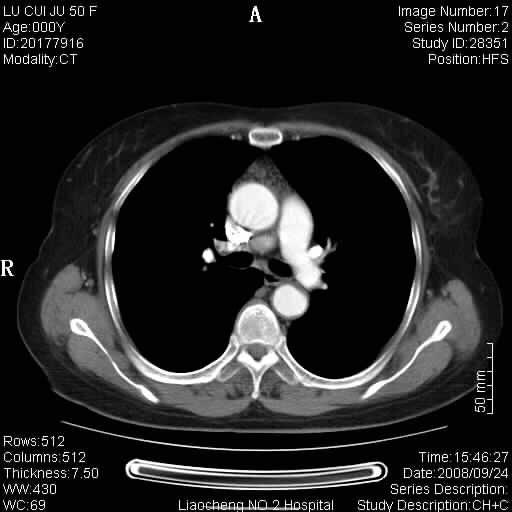

标题: CT15870:F50Y,纵膈占位,是不是胸腺瘤,请各位高手讨论。

临床表现为重症肌无力;ct增强扫描可见前纵膈胸腺部位弥漫性簇状软组织节结灶,不知道是不是胸腺瘤,请各位高手讨论。

胸腺外缘稍向外突,未见确切占位改变。结合临床考虑胸腺增生可能性大。